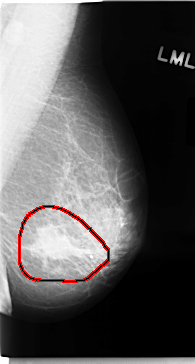

FILE: C_0050_1.LEFT_MLO.OVERLAY

TOTAL_ABNORMALITIES 1

ABNORMALITY 1

LESION_TYPE MASS SHAPE IRREGULAR MARGINS SPICULATED

ASSESSMENT 5

SUBTLETY 5

PATHOLOGY MALIGNANT

TOTAL_OUTLINES 1

BOUNDARY